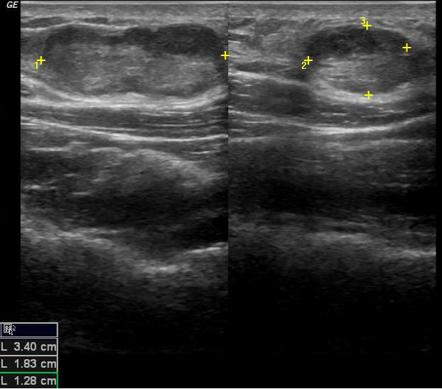

Диагностика липосаркомы включает физический осмотр, медицинскую историю, а также визуализирующие исследования, такие как УЗИ, КТ или МРТ. Для подтверждения диагноза может потребоваться биопсия. Лечение обычно включает хирургическое удаление опухоли, а в некоторых случаях может потребоваться химиотерапия или радиотерапия, особенно если опухоль не поддается полному удалению или если есть риск рецидива.